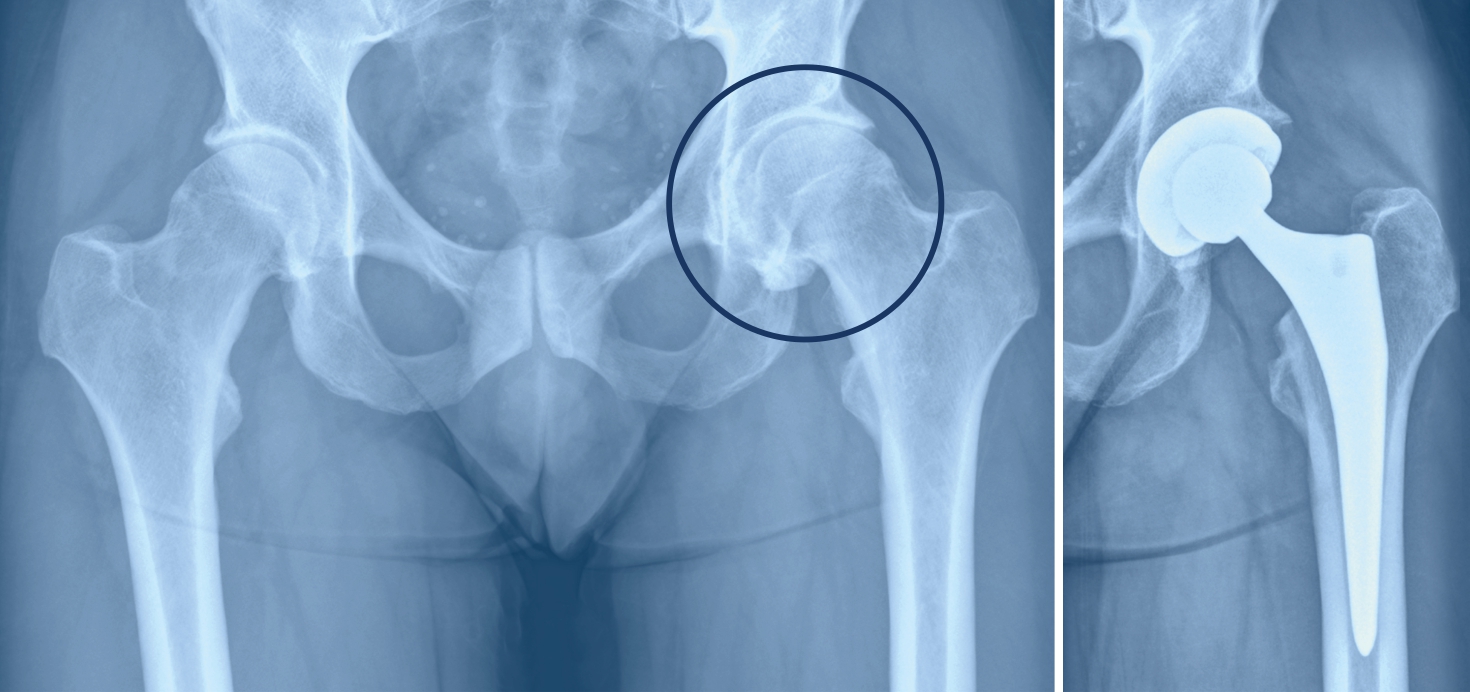

Bild links: Deutlich ausgepräfte einseitige Hüftarthrose.

Bild rechts: Eingesetzte Hüfttotalprothese.

Hüftgelenkarthrose

Bei einer Hüftgelenkarthrose wird der Knorpelüberzug auf dem Kopf des Oberschenkelknochens und im Bereich der Hüftpfanne im Laufe der Zeit immer dünner. Dies verursacht Schmerzen, die insbesondere bei längerem Gehen oder morgens nach dem Aufstehen, aber auch im Ruhezustand auftreten können. Ausserdem nimmt die Beweglichkeit der Hüfte ab, bis sie schliesslich fast steif ist. Alltägliche Verrichtungen wie Socken anziehen oder Schnürsenkel binden, kann man dann fast nicht mehr selbstständig ausführen. Ein künstliches Hüftgelenk schafft hier Abhilfe, so dass sich die Lebensqualität wieder deutlich erhöht.